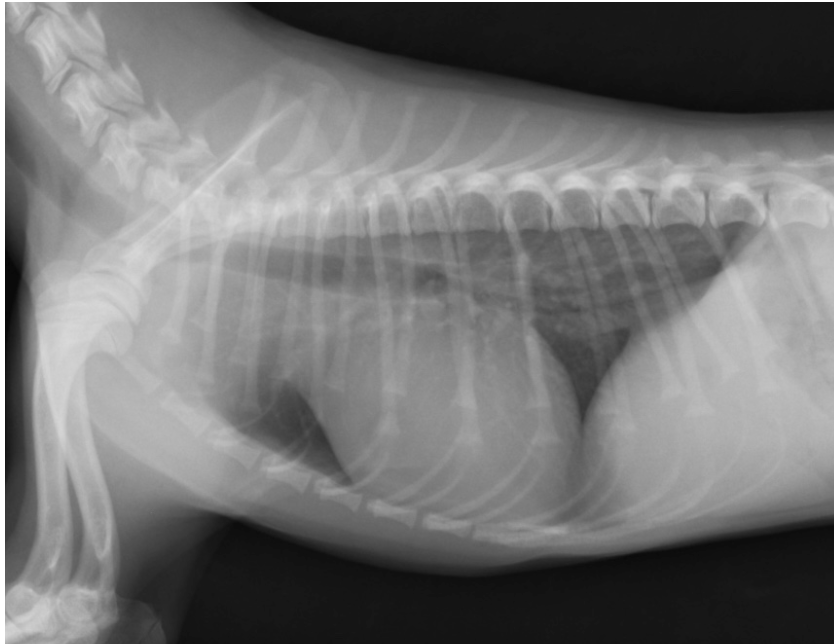

動脈管開存症は、生まれつきの心臓病で放っておいた場合の1年間での死亡率は70%と、致命率が非常に高い病気です。お母さんのお腹の中にいた時には、大事な役割をしていた動脈管が、出生後も血管が残ったままになってしまい、大動脈から全身に送り出される血液の大部分がが肺に流れ込んでしまう事態がおきます。すると、全身は血液が送られずに疲れやすく、肺は異常な量の血液が流れ込むので、鬱血という血液が大渋滞を起こすような状態になります。

酷くなると肺に水が溜まる肺水腫という左心不全症状が出現します。これは陸にいながら溺れているほど苦しい状態と言われております。

今回のワンちゃんは、生後5ヶ月齢で自宅に来た際予防接種を実施したタイミングで、心臓に異常な音が聞こえるということで診断を受け、当院へ紹介来院しております。

前回ご紹介したワンちゃんは開胸という方法で手術しております。こちらも確実に治せる方法ではありますが、胸を大きく切るため非常に侵襲は高くわんちゃんには負担になります。今回のワンちゃんは体重がギリギリですが、カテーテルでの治療を受けられるサイズでした(1.6kgくらい)。なので開胸せずに治せる方法で治療を実施します。カテーテルを使用し、コイルというもので穴を塞ぐ手術となります。

足の血管に小さく切開を実施し、カテーテルを心臓まで挿入。造影という血管を光らせる薬で動脈管をはっきりと描出し、タイプがコイルの適応であればコイルで治療できます。今回は造影後にコイルの適応タイプだったためそのままコイルを入れ手術終了。1hr30min程度でコイルひとつを入れ閉塞を確認したの後終了できています。